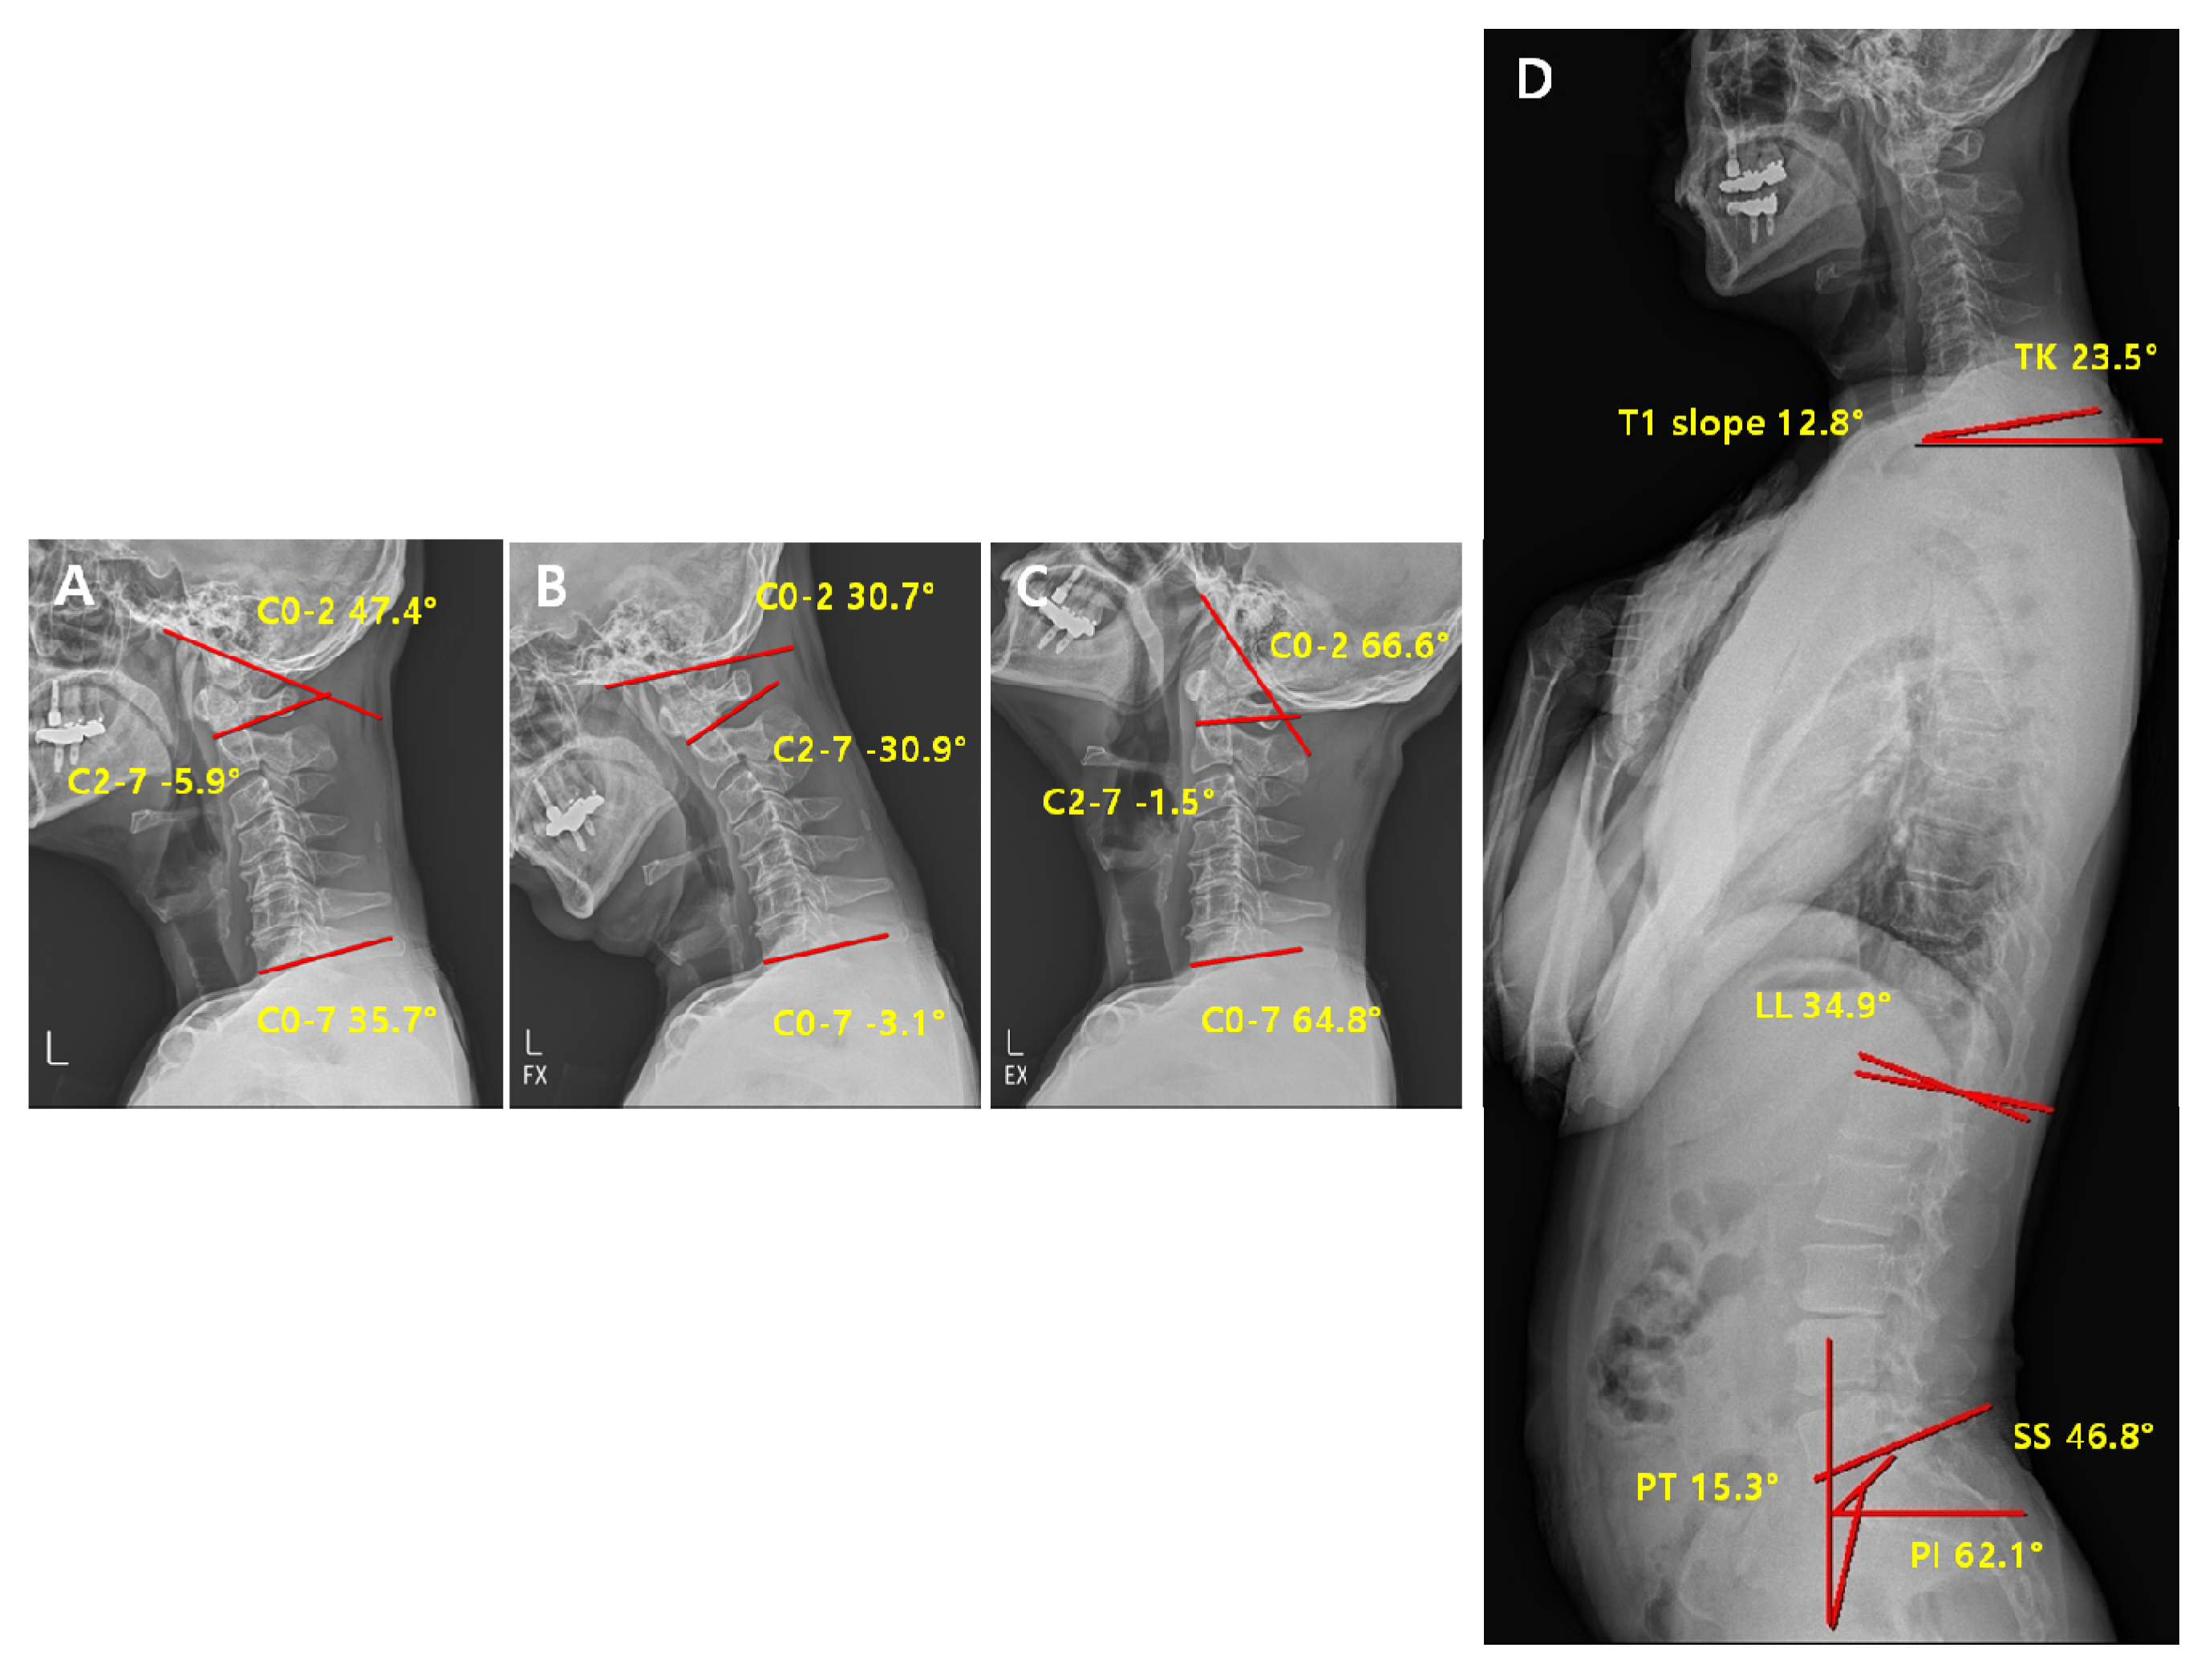

2.3. Radiographic Measurement

2.4. Radiological Analysis